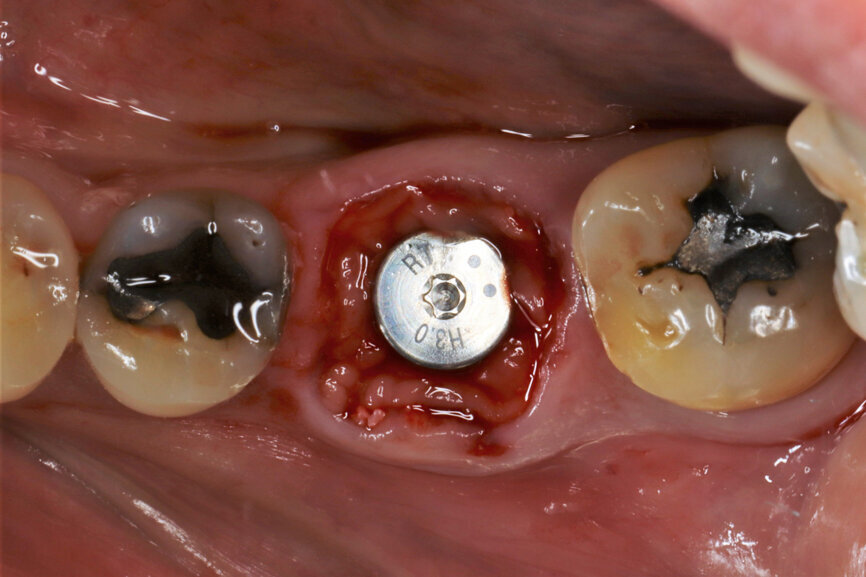

Fig. 5: Socket dimensions preserved.

It was possible to verify solid interradicular bone availability (Fig. 5), extending further the limits of the root apices and allowing for a centrally oriented osteotomy. The implant bed preparation started with the use of a needle drill at 800 rpm, followed by the ⌀ 2.2 mm and ⌀ 2.8 mm drills (Figs. 6–10). The implant was placed with the use of ratchet and torque control, reaching the desired final position at a 50 N cm torque value (Figs. 11–13). The socket was then augmented with bovine-derived bone substitute impregnated with advanced platelet-rich fibrin (A-PRF) and finalised with sutures to keep the A-PRF application immobile, and a 3 mm healing abutment was placed (Figs. 14–17).